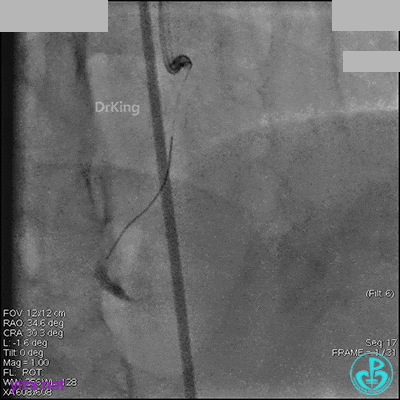

1周后再次上台,右冠脉3级血流,3段局限性严重狭窄,内膜模糊,应该是上次操作夹层遗留下的血肿。

先处理前降支开口严重狭窄并顺利植入前降支到左主干支架。